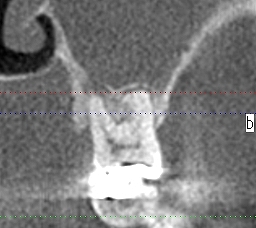

ブログ一覧|広島市安佐南区の歯科医院 ブログ一覧 トップ ブログ一覧 お知らせ スタッフブログ ブログ一覧 2018/01/26 4歳2ヶ月の時に右下Dの萌出困難な歯を診させていただいたのですが。 何もできず、それから9歳になろうかとの時期で来院されました。 歯はますます埋まっていました。何が原因でこうなるのかはわからない所で、時に教わる経験をすることもあります。 どうしてこんな現象になるのだろうと考えることもあります。 2018/01/26 噛み合せにより歯はこんなになります。 2018/01/26 正中口蓋嚢胞。 2年後自然消失。 2018/01/26 親不知を抜歯すると手前の歯が生えてきます。 2018/01/25 歯性上顎同炎 2018/01/25 歯性上顎同炎 2018/01/25 歯性上顎同炎 2018/01/25 親不知の完全水平埋伏歯抜歯。 << 1 2 3 4 5 … 766 767 768 769 770 … 870 871 872 873 874 >> Web診療予約 初めての方へ 選ばれ続ける理由 院内設備について 歯が痛いしみる一般歯科 歯がぐらぐらする歯周病 健康な歯を保ちたい予防歯科 子供の虫歯予防をしたい小児歯科 銀歯をセラミックに審美歯科 白い歯を目指しませんか?ホワイトニング 矯正専門医がいるので安心矯正歯科 抜けた歯を補いたいインプラント・入れ歯 医院案内 スタッフ紹介 メリィハウス歯科クリニックオフィシャルホームページ ラベンダー歯科クリニックオフィシャルホームページ お知らせ・ブログ ホーム 診療科目 一般歯科 歯周病治療 予防治療 小児歯科 審美治療 ホワイトニング 矯正歯科 入れ歯・インプラント マウスピース矯正 初めての方へ 院長・スタッフ 設備紹介 医院案内・アクセス メニューを閉じる